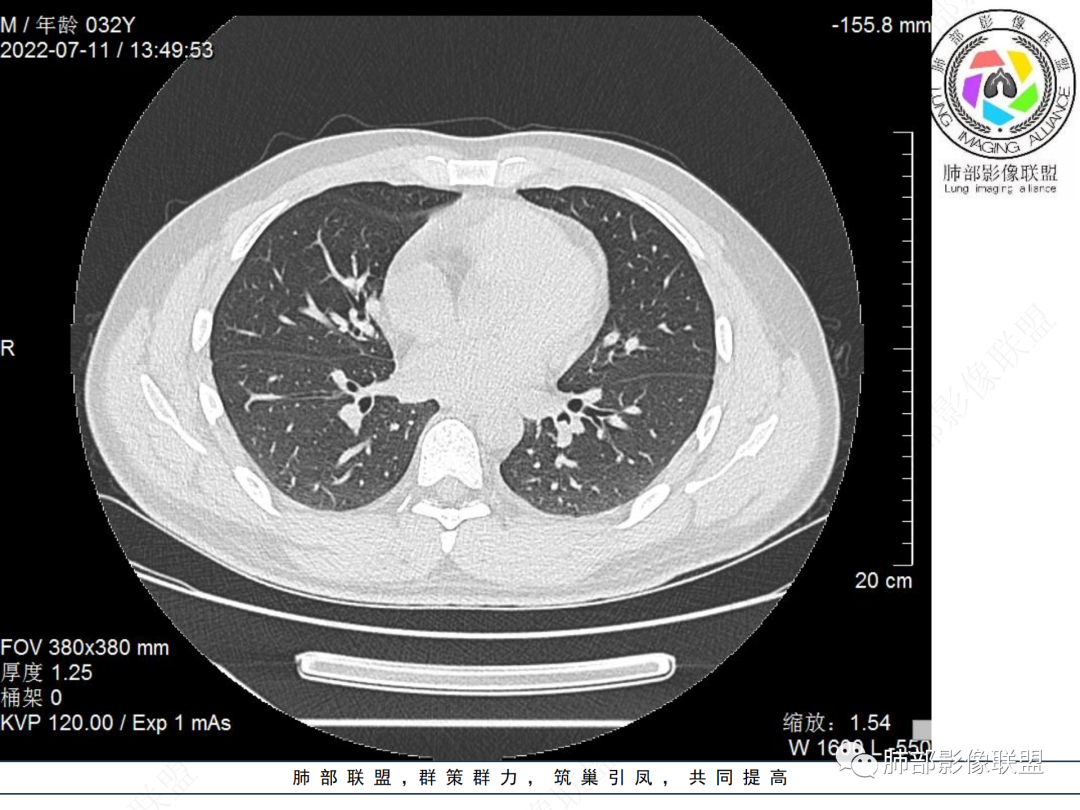

左肺下叶后基底段开口处结节,边缘光滑清楚,没有增强扫描,年轻男性患者痰血三天,考虑1.良性病变:腺瘤、错构瘤、平滑肌瘤

左肺下叶外后基底段气管内见结节状影,边缘部分清晰。考虑错构瘤,待排恶性病变。

左肺下叶气管内外占位病变,咯血病史,考虑类癌,粘表待排。

青年男性,左肺下叶后基底段支气管开口软组织结节,边缘光整,气管镜提示质软,易出血,考虑类癌

左肺下叶气道腔内占位,远端无花花草草,疾病谱:鳞,类癌,粘表,腺样囊腺癌,小,无增强,不好判断,临床咯血,选类癌。

左肺下叶后基底段开口处结节影,边缘光滑,患者年龄较小,首选类癌

左肺下叶后基底段开口处腔内见壁结节,花生米样,宽基底,补充增强及矢状位重建,确定我无向壁外突破浸润生长,另见强化的特点,临床触之易出血,类Ca可能性大。

年轻男性,咳血,左肺下叶后基底段支气管腔内结节,边缘光滑,首先考虑青年三件套,类癌大于粘液表皮样癌,支气管镜质软,触之易出血,鉴别血管瘤,平滑肌瘤

左肺下叶后基底段开口部结节,密度较均匀一致,边缘较光整,目测密度偏低,支气管镜示:质软、触之易出血,考虑恶性,类癌。

左肺下叶后基底段支气管腔内结节,有蒂,容易出血,先考虑良性病变,肉芽组织型血管瘤,与类癌鉴别。